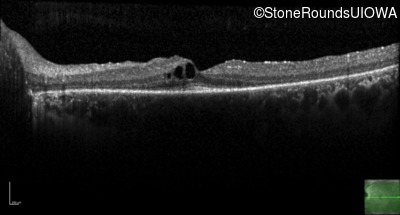

Optical Coherence Tomography - Left -

20/20 -2

Exemplar / OCT Stack